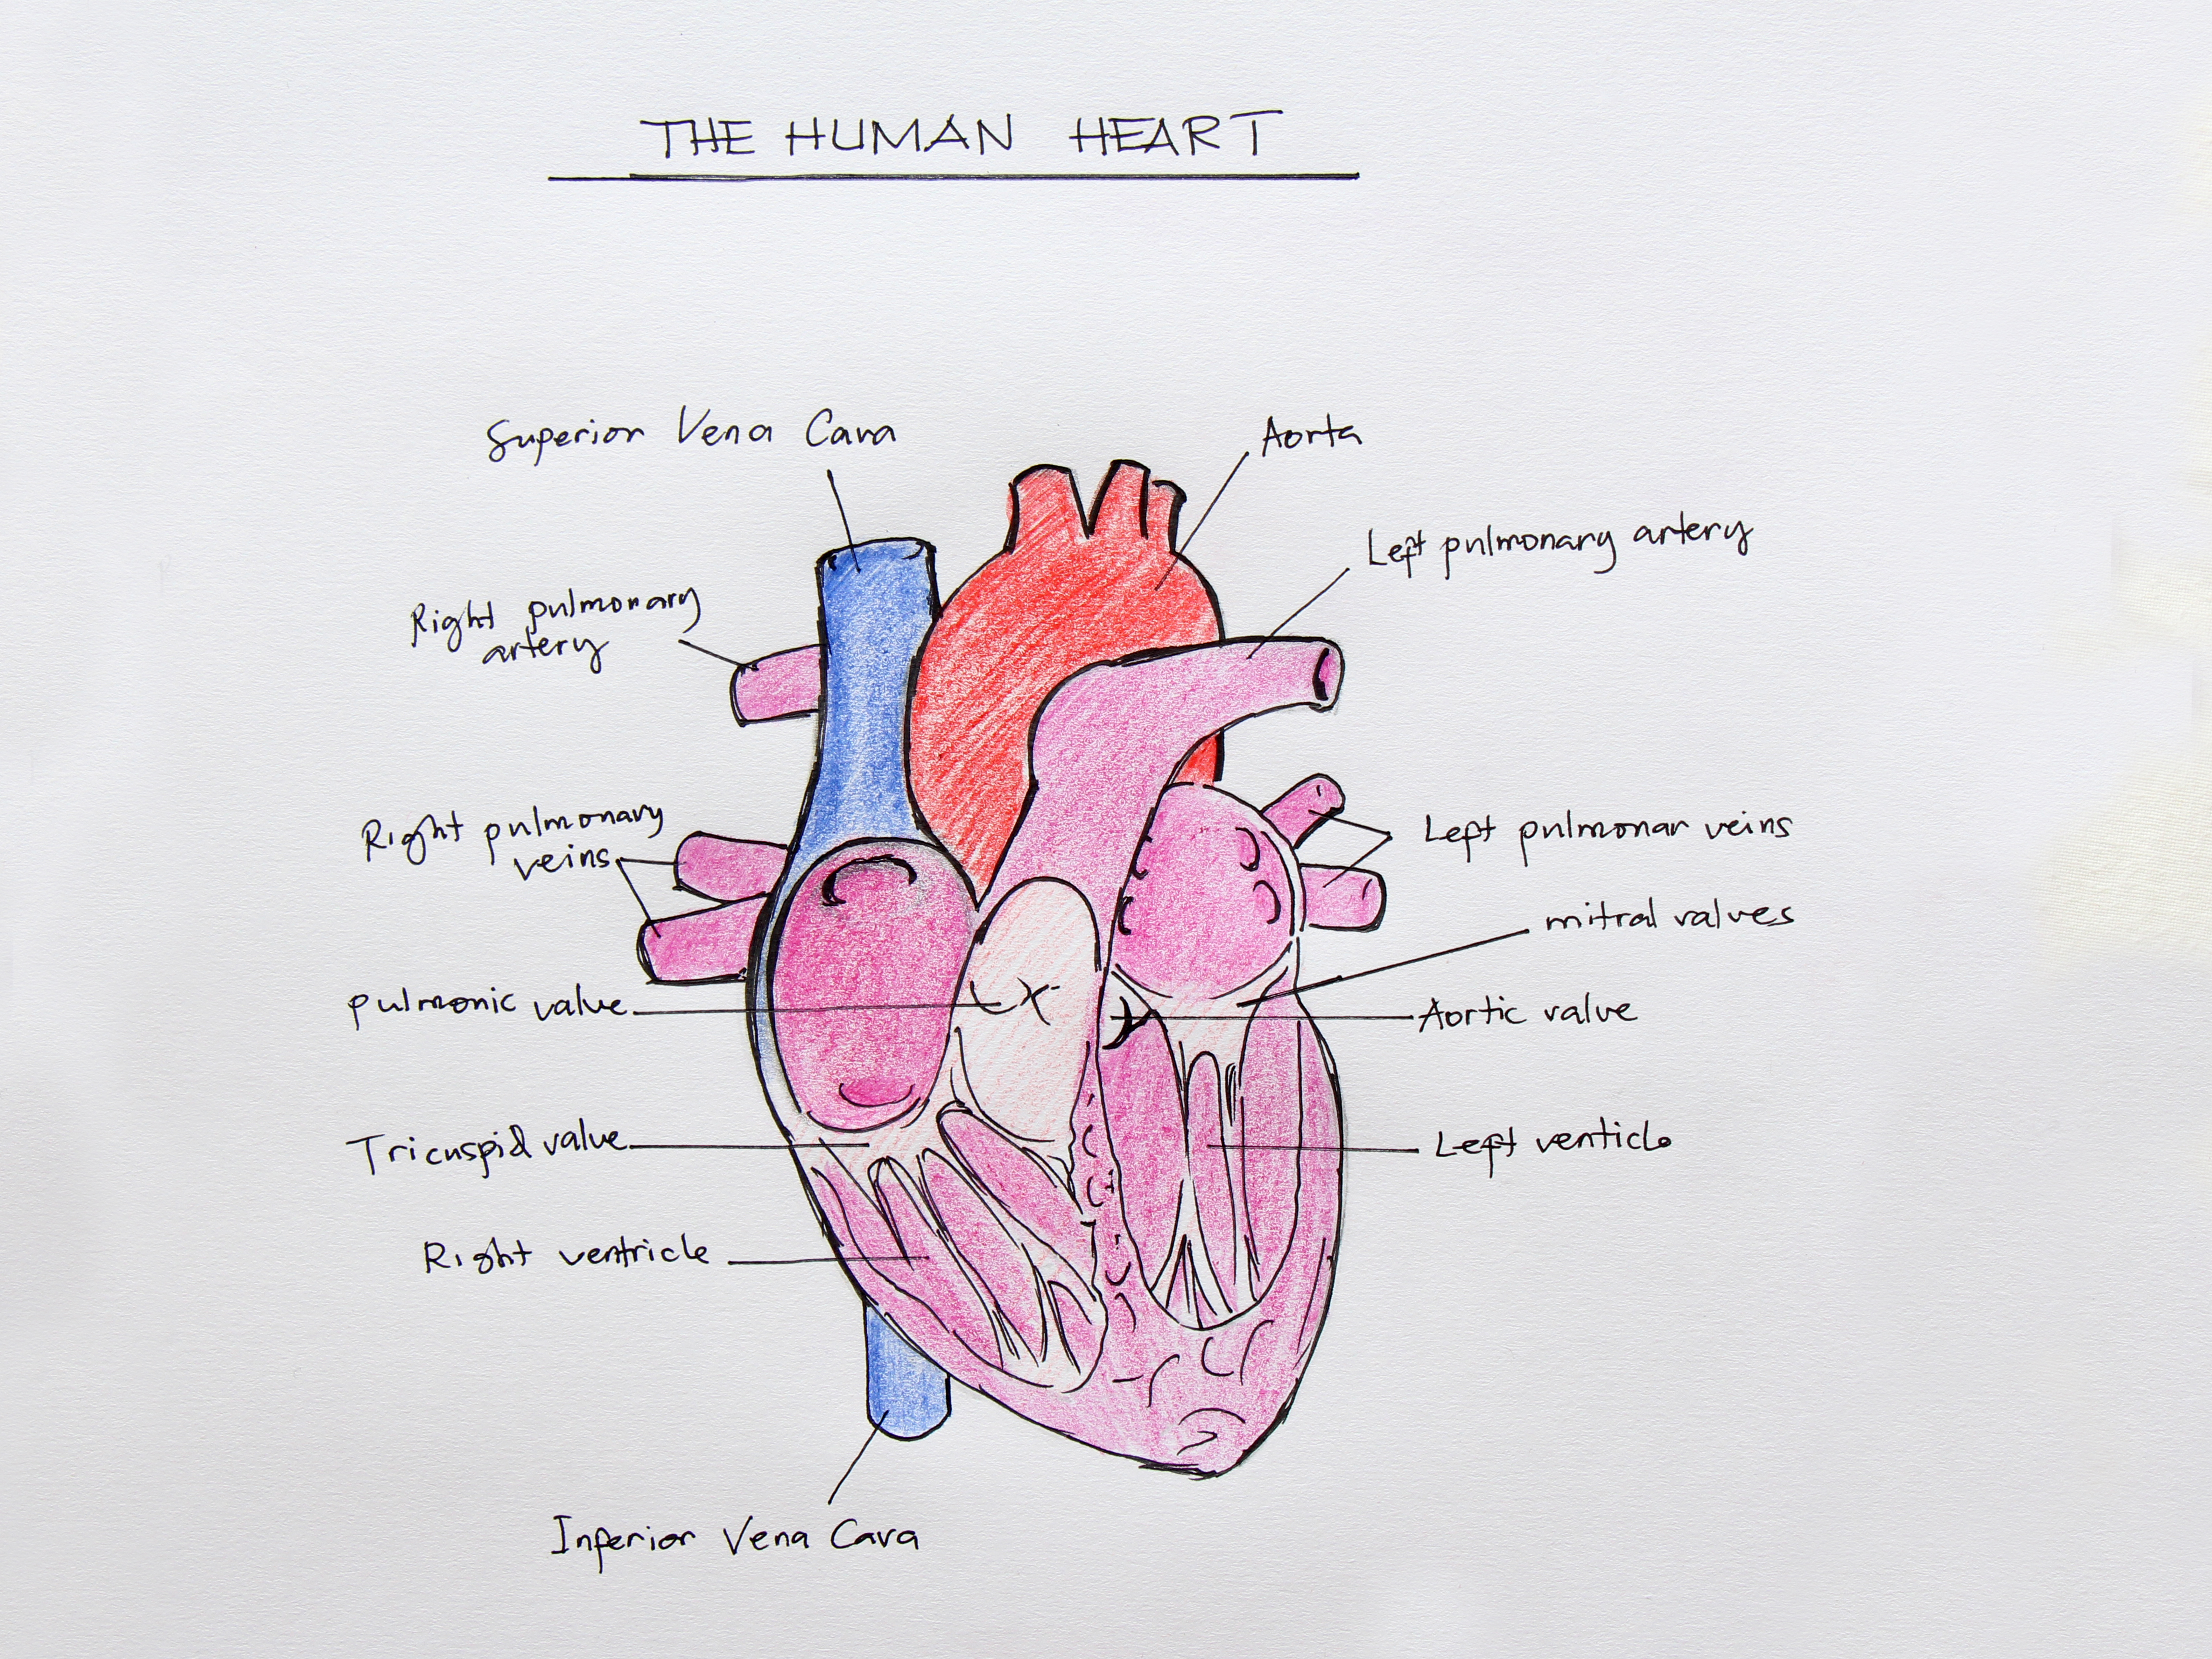

What are the parts that make up a human heart? Diagrams and More | Human heart diagram, Heart  Human heart by kortney16 on DeviantArt

Human heart by kortney16 on DeviantArt  Human Heart-Gross structure and Anatomy - Online Biology Notes

43+ Human Heart Handmade Diagram PNG | Diagram of Everythings  Human Heart Diagram Without Labels - koibana.info | Human heart diagram, Heart diagram, Human

How to draw human heart diagram drawing || Heart anatomy drawing with color || easy - step by step  For You With Love | Heart drawing, Anatomical heart drawing, Human heart drawing

Colorful Hand Drawn Illustration Of Human Heart Anatomy Stock Illustration - Download Image Now  Anterior view of human heart anatomy Poster Print by Photon Illustration/Stocktrek Images